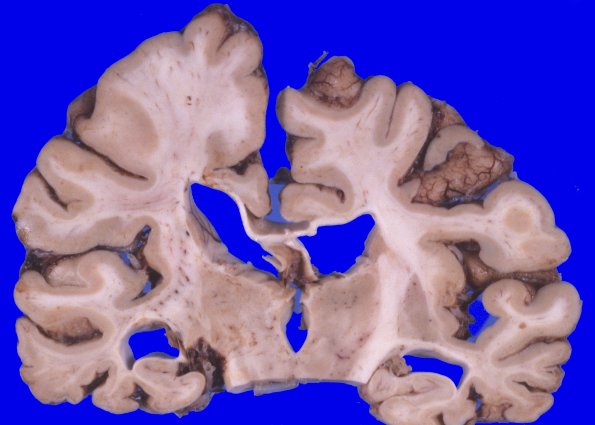

Coronal sections confirm the degree of diffuse cortical atrophy with narrow gyri and wide sulci with a large amount of ventricular dilatation and blunting. The cerebral white matter is diffusely firm to palpation. The corpus callosum is extremely thin.